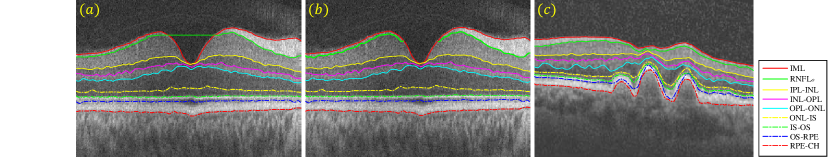

In this section, we will provide an overview of the state-of-the-art methods (i.e. parallel double snakes [14], Chiu’s method [15], OCTRIMA3D [29, 30], Dufour’s method [27]) that will be compared with our proposed GDM in Section 3. For a complete review on the subject, we refer the reader to [39]. Among the four methods reviewed, the first two can only segment B-scans, while the latter two are able to extract retinal surfaces from volumetric OCT data. We note that the term ‘surface’ refers to a set of voxels that fall on the interface between two adjacent retinal layer structures. The retinal layer boundaries to be delineated are shown in Figure 2.

where the image energy ( is the image gradient operator) attracts the parametric curve towards one of retinal borders of the input B-scan , whilst handles curve which is parallel to . The internal energy imposes both first and second order smooth regularities on the central curve , with and respectively controlling the tension and rigidity of this curve. is a parallelism constraint imposed on and . Nine retinal borders have been delineated by the method, i.e., ILM, RNFLo, IPL-INL, INL-OPL, OPL-ONL, ONL-IS, IS-OS, OS-RPE and RPE-CH.